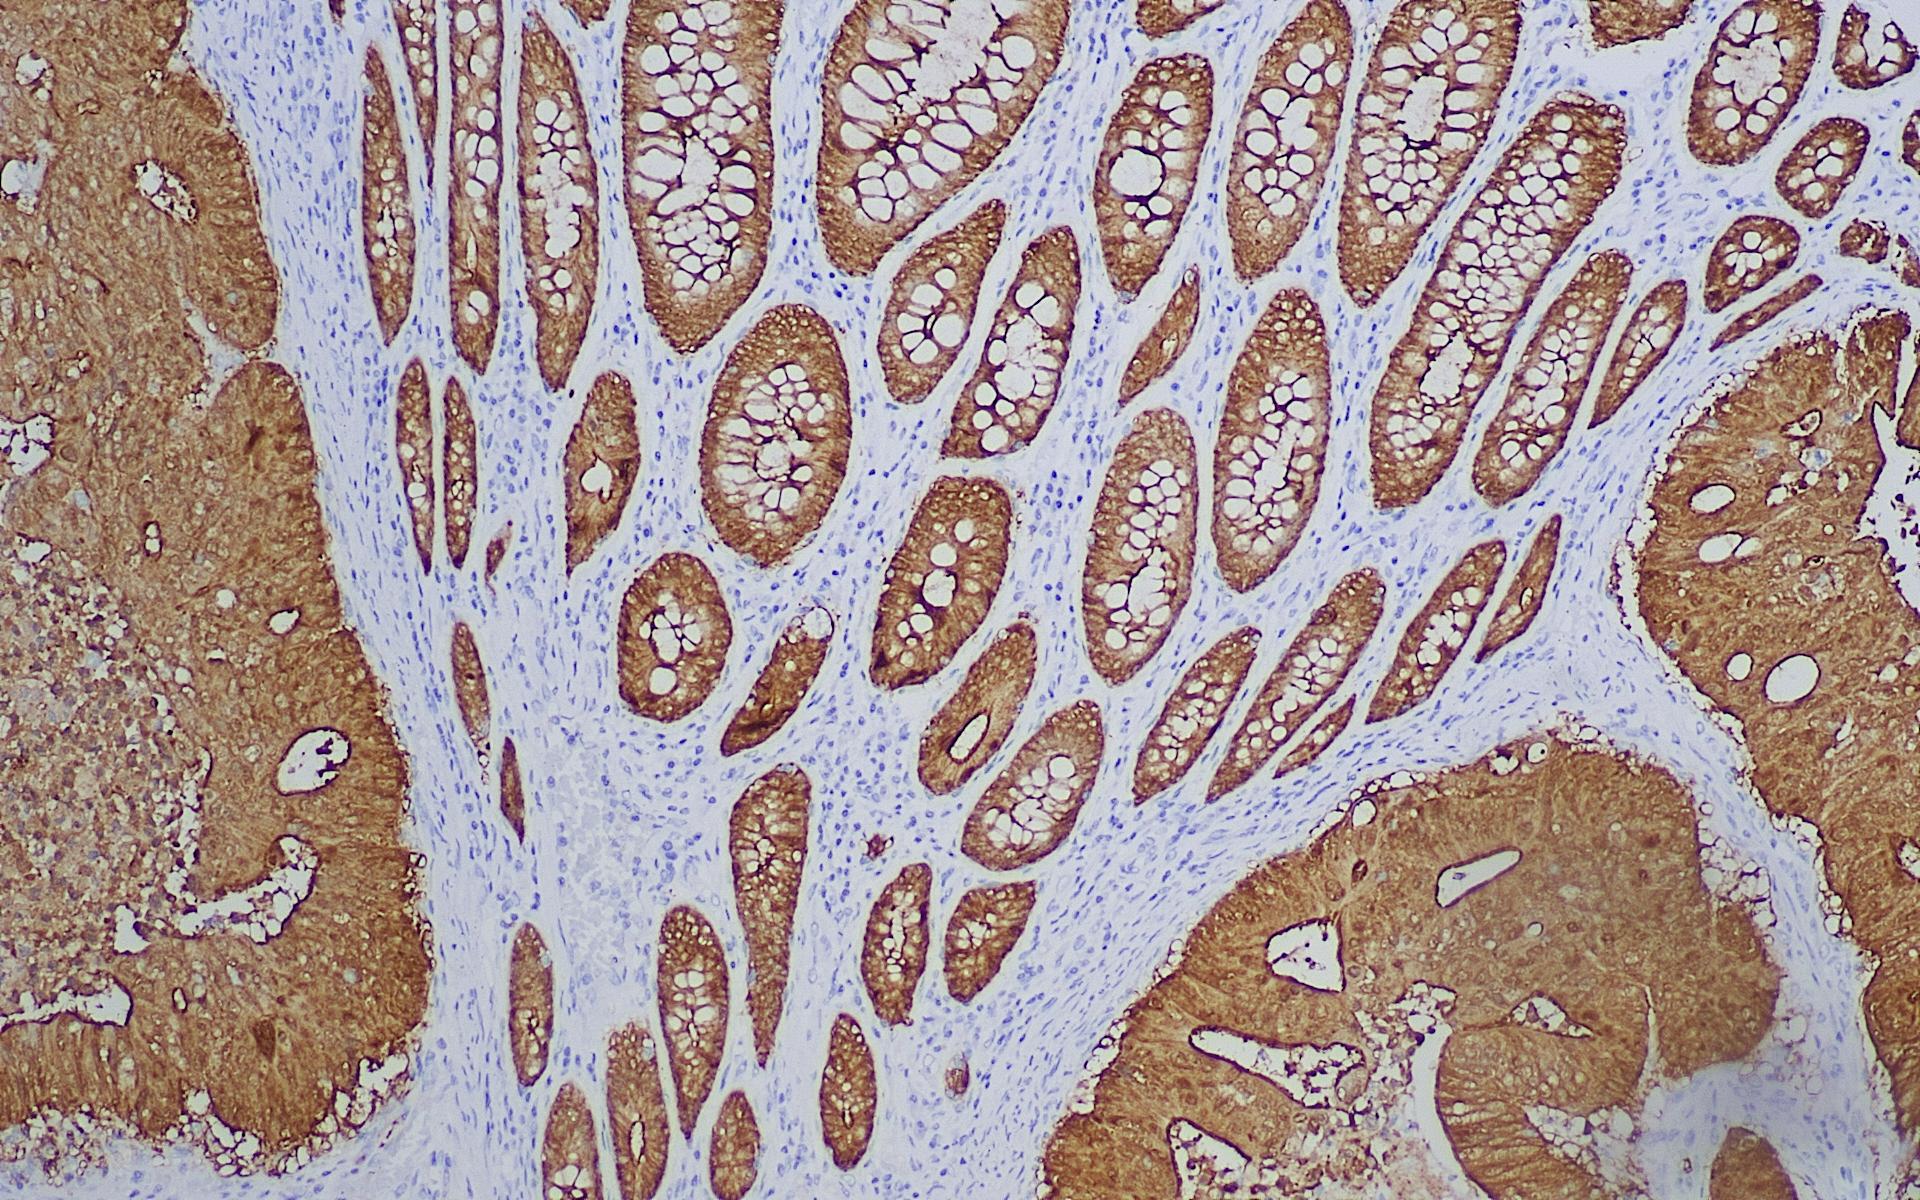

• Villin结直肠

Villin是与刷状缘微绒毛的微丝束有关的一种胃肠道相关性细胞骨架蛋白。正常组织中,Villin通常只表达于有刷状缘的细胞上,如胃肠道上皮细胞、胰腺和胆管上皮细胞以及肾实质的上皮细胞中(特别是近曲小管)。Villin作为肠道特异性参考依据,与CDX2联合应用,可用于肠上皮来源肿瘤与非肠上皮肿瘤的研究。Villin 也可作为胃肠道神经内分泌肿瘤研究的参考指标。